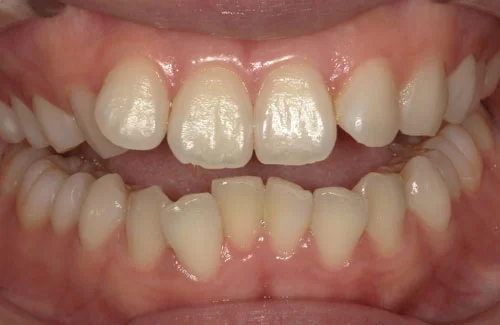

<症例5>上の前歯が飛び出しているお悩み

下の歯のガタガタと若干の前歯のズレの矯正でした。

アーチが綺麗に揃ったことにより見た目が改善されたほか、ステインや歯石も付きにくくなりました。

患者様と症状

主訴:下の歯がガタガタ

性別・年齢:20代女性

問題点:叢生、ディープバイト

診断:前歯部の叢生を伴うアングルⅠ級の不正咬合

主なリスク:矯正中一時的に咬合しにくくなる、歯肉退縮

症状:叢生(そうせい) 過蓋咬合(かがいこうごう)

治療内容

治療期間:3ヶ月

治療費用:330,000円(税込)

プラン:8枚コース/アーリープラン

抜歯:無し

再診治療費:無し

追加治療費:無し

保定装置費:無し

治療前後の写真